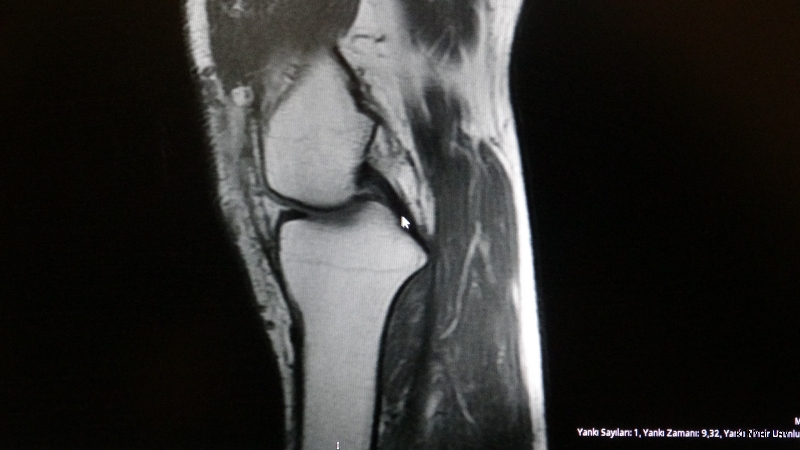

Ortopedi polikliniklerine en sık ayak bileği, diz ve omuz yaralanmalarıyla başvurulduğunu belirten Demirbaş, futbol nedeniyle yaralanma oranlarının da ilk sırada yer aldığını söyledi. Konuya ilişkin Demirbaş, "Futbolda menisküs yırtıkları, ön çapraz bağ yırtıkları, iç ve dış yan bağ yaralanmaları, aşil tendon kopmaları ve ayak bileği bağ yaralanmaları çok sık görülüyor. Ayrıca spora bağlı kırıklar da önemli bir yer tutuyor" ifadelerini kullandı.